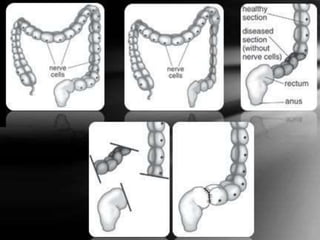

Normal colon Hirschsprung disease

Hirschsprung disease is a congenital disorder which is

characterized by absence of the parasympathetic

ganglionic nerve cells within the muscle wall of the

intestinal tract, usually at the distal ends of the colon,

resulting in functional obstruction with dilation and

hypertrophy of proximal colon.

The level of hirschsprung's disease include:-

 Short-segment: Missing ganglion cells in the rectum

and sigmoid colon (the last segment of the colon).